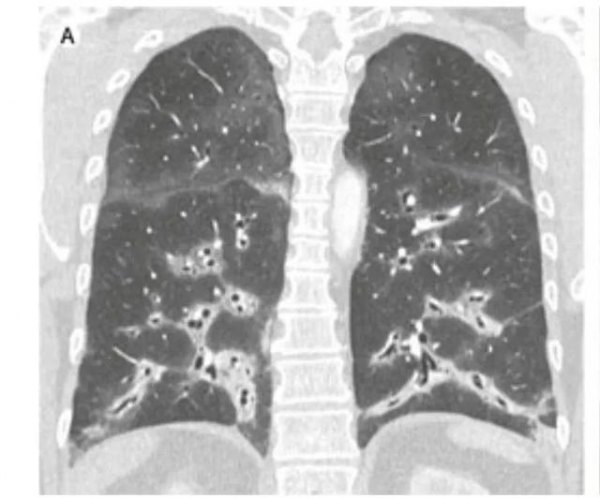

胸部高分辨率CT掃描(圖)顯示肺下葉病變明顯,支氣管血管周圍有雙側實變,機化性肺炎。

實驗室檢查:沒有任何感染或風濕病病因的證據:C反應蛋白濃度和白細胞計數正常。過敏性肺炎和膠原性血管病抗體篩查陰性。支氣管肺泡灌洗液70%為淋巴細胞。

經支氣管肺活檢:組織病理學檢查證實為機化性肺炎,夾雜著含有色素的巨噬細胞,表明有異物吸入。

臨床診斷:電子煙相關肺損傷